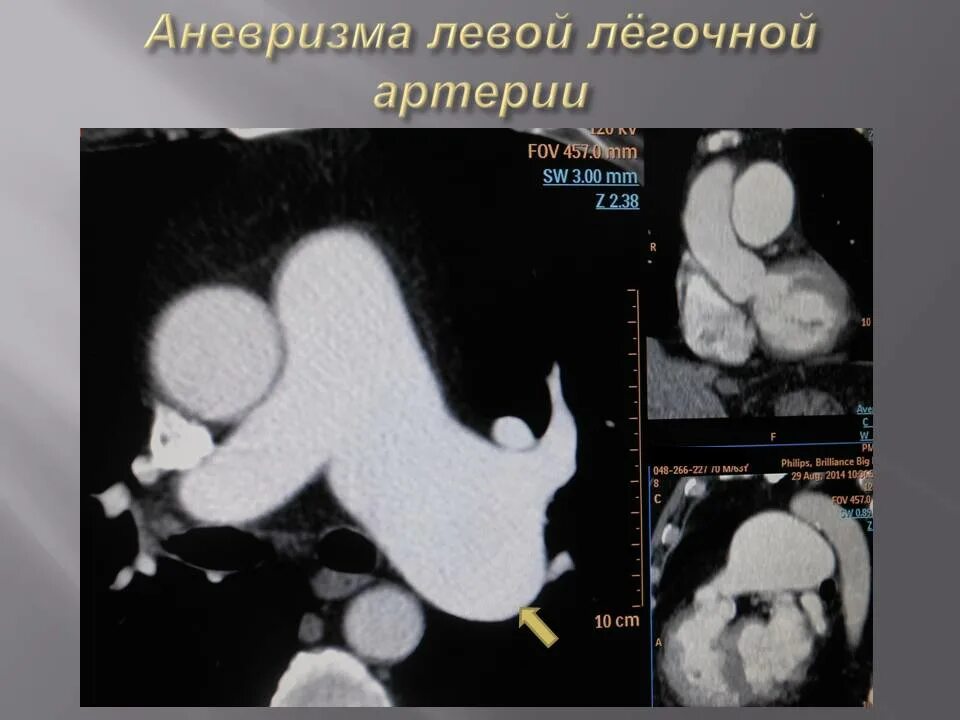

Легочный ствол на кт